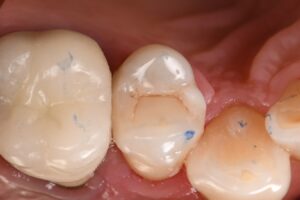

It’s always difficult to decide which vertical hairline fractures to chase in a compromised peripheral enamel rim. Chasing and selectively removing the significant hairline fractures with penetration past the DEJ ensures that these superhighways are sealed and don’t have an opportunity to seed caries insidiously.

#VocoGrandioSO #GarrisonCompositight